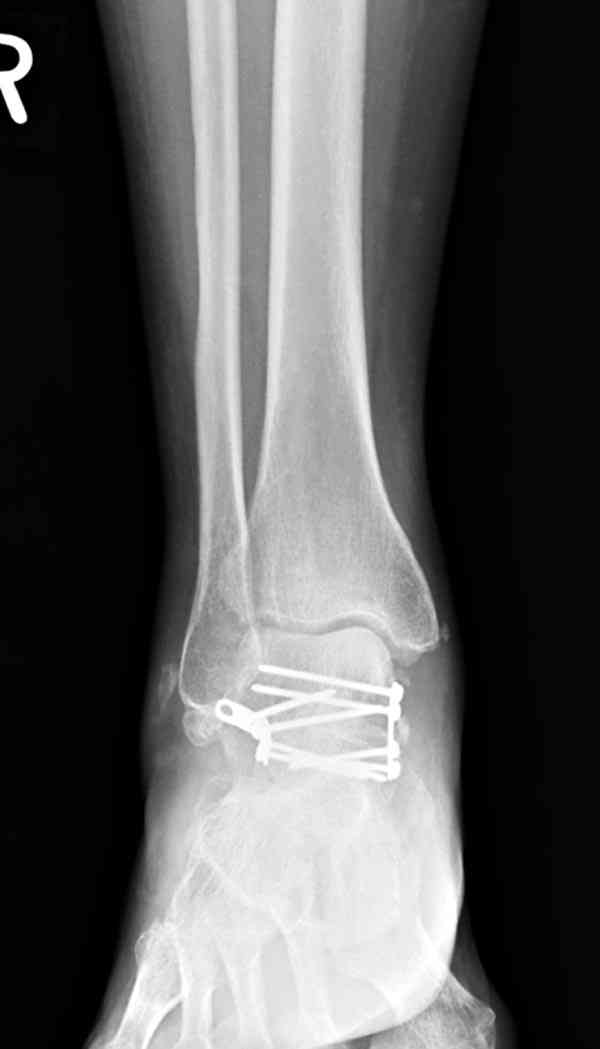

Случай с множественным оскольчатым переломом тарана оперированный из двойного доступа.

Через 2 мес.:

Через 8 мес.:

Через 14 мес.: